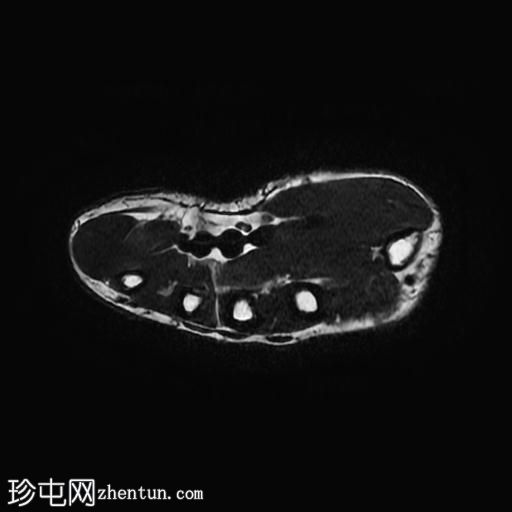

轴位

T2加权像

5.jpg